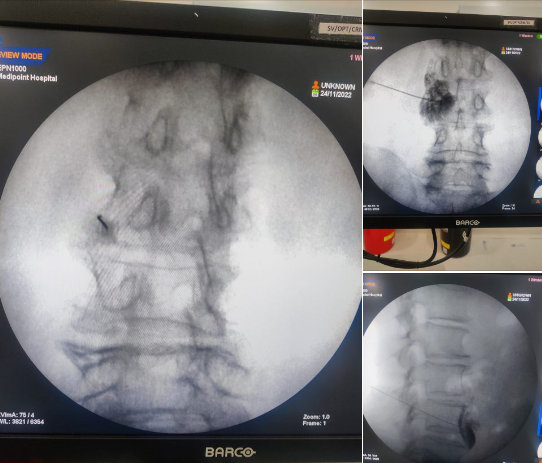

Sometimes sympathetic nerves can continue to transmit pain even after healing from surgery or injury, which is known as Chronic Regional Pain Syndrome. (These nerves take part in regulating everything from neuropathic pain to sweating, body temperature) When this happens, patients experience severe burning pain, swelling, and changes in skin color, texture, and temperature. A Lumbar Sympathetic Block is used to reduce the symptoms of CRPS in lower limbs. The injection involves a combination of an anesthetic medication plus a corticosteroid which is injected near the spine to block the nerves. #chronicpain #pain #CRPS #Causalgia #RSD #Swelling #leg #hands #lumbar #sympathetic block #painblock #painspecialist #drpriyarathi#